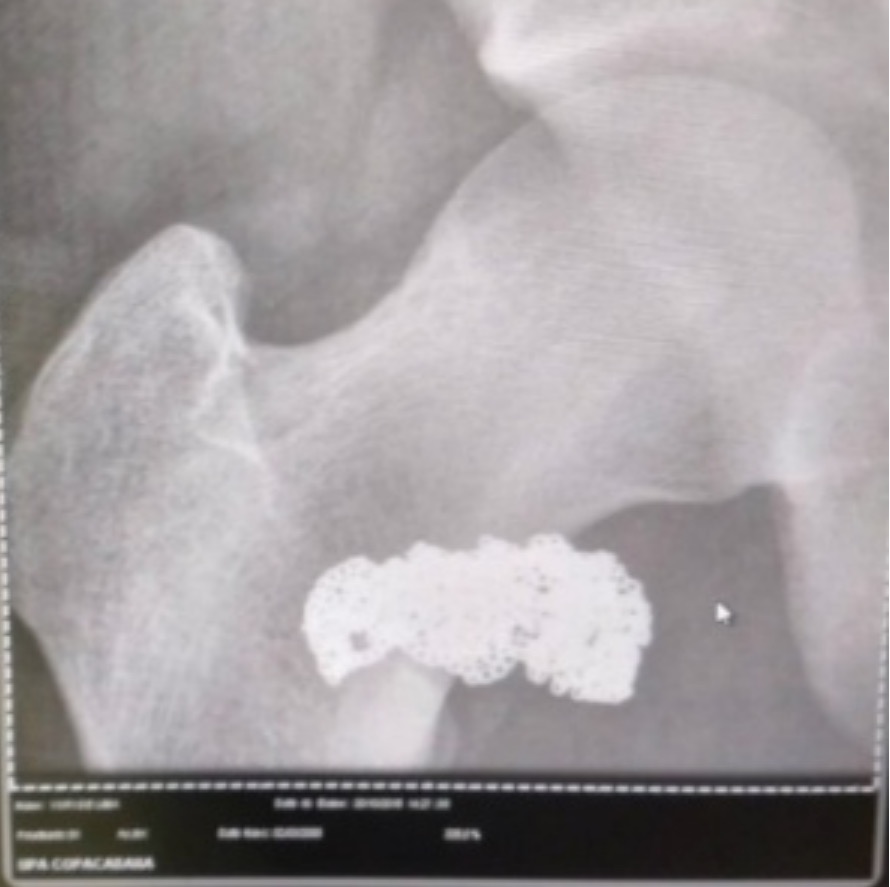

Um homem foi preso por furtar um cordão de ouro em Ipanema, no Rio de Janeiro. Para não ser pego em flagrante, ele engoliu o objeto e alegou inocência, mas um exame de raio-x provou que ele havia realmente cometido o crime.

Diante da situação, os agentes conseguira, abordar um suspeito e conduziram e encaminharam o homem a uma Unidade de Pronto Atendimento da Região (UPA) em Copacabana. Lá, ele foi submetido a um exame de imagem que mostrou o objeto na região de seu abdômen e saiu do local preso em flagrante por furto.